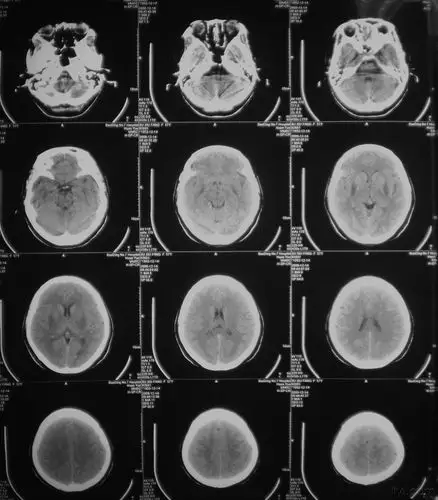

大家看看这双侧基底节区低密度影是什么病变?

累及双侧基底节的十大病变